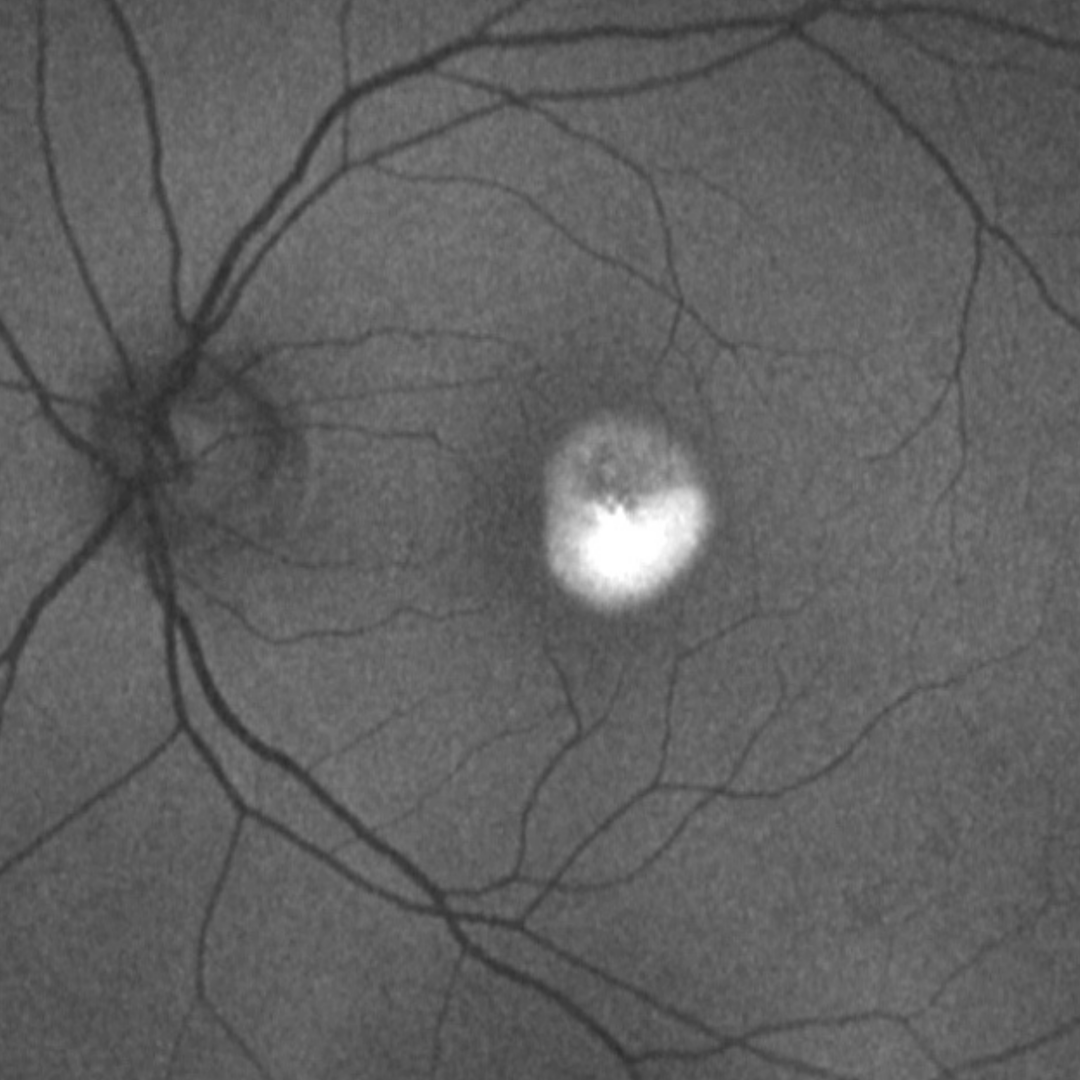

2. Vitelliform stage: A classic "egg yolk lesion" is visible in the fundus, usually ½-2 disc diameter in size. On OCT, the lesion is seen to be sub-retinal in location and vision is unaffected at this stage.

Case 1: Vitelliform stage

A 54-year-old Caucasian male with visual acuity of 6/6 (20/20) in each eye.

Colour fundus photograph and red-free image (right eye)